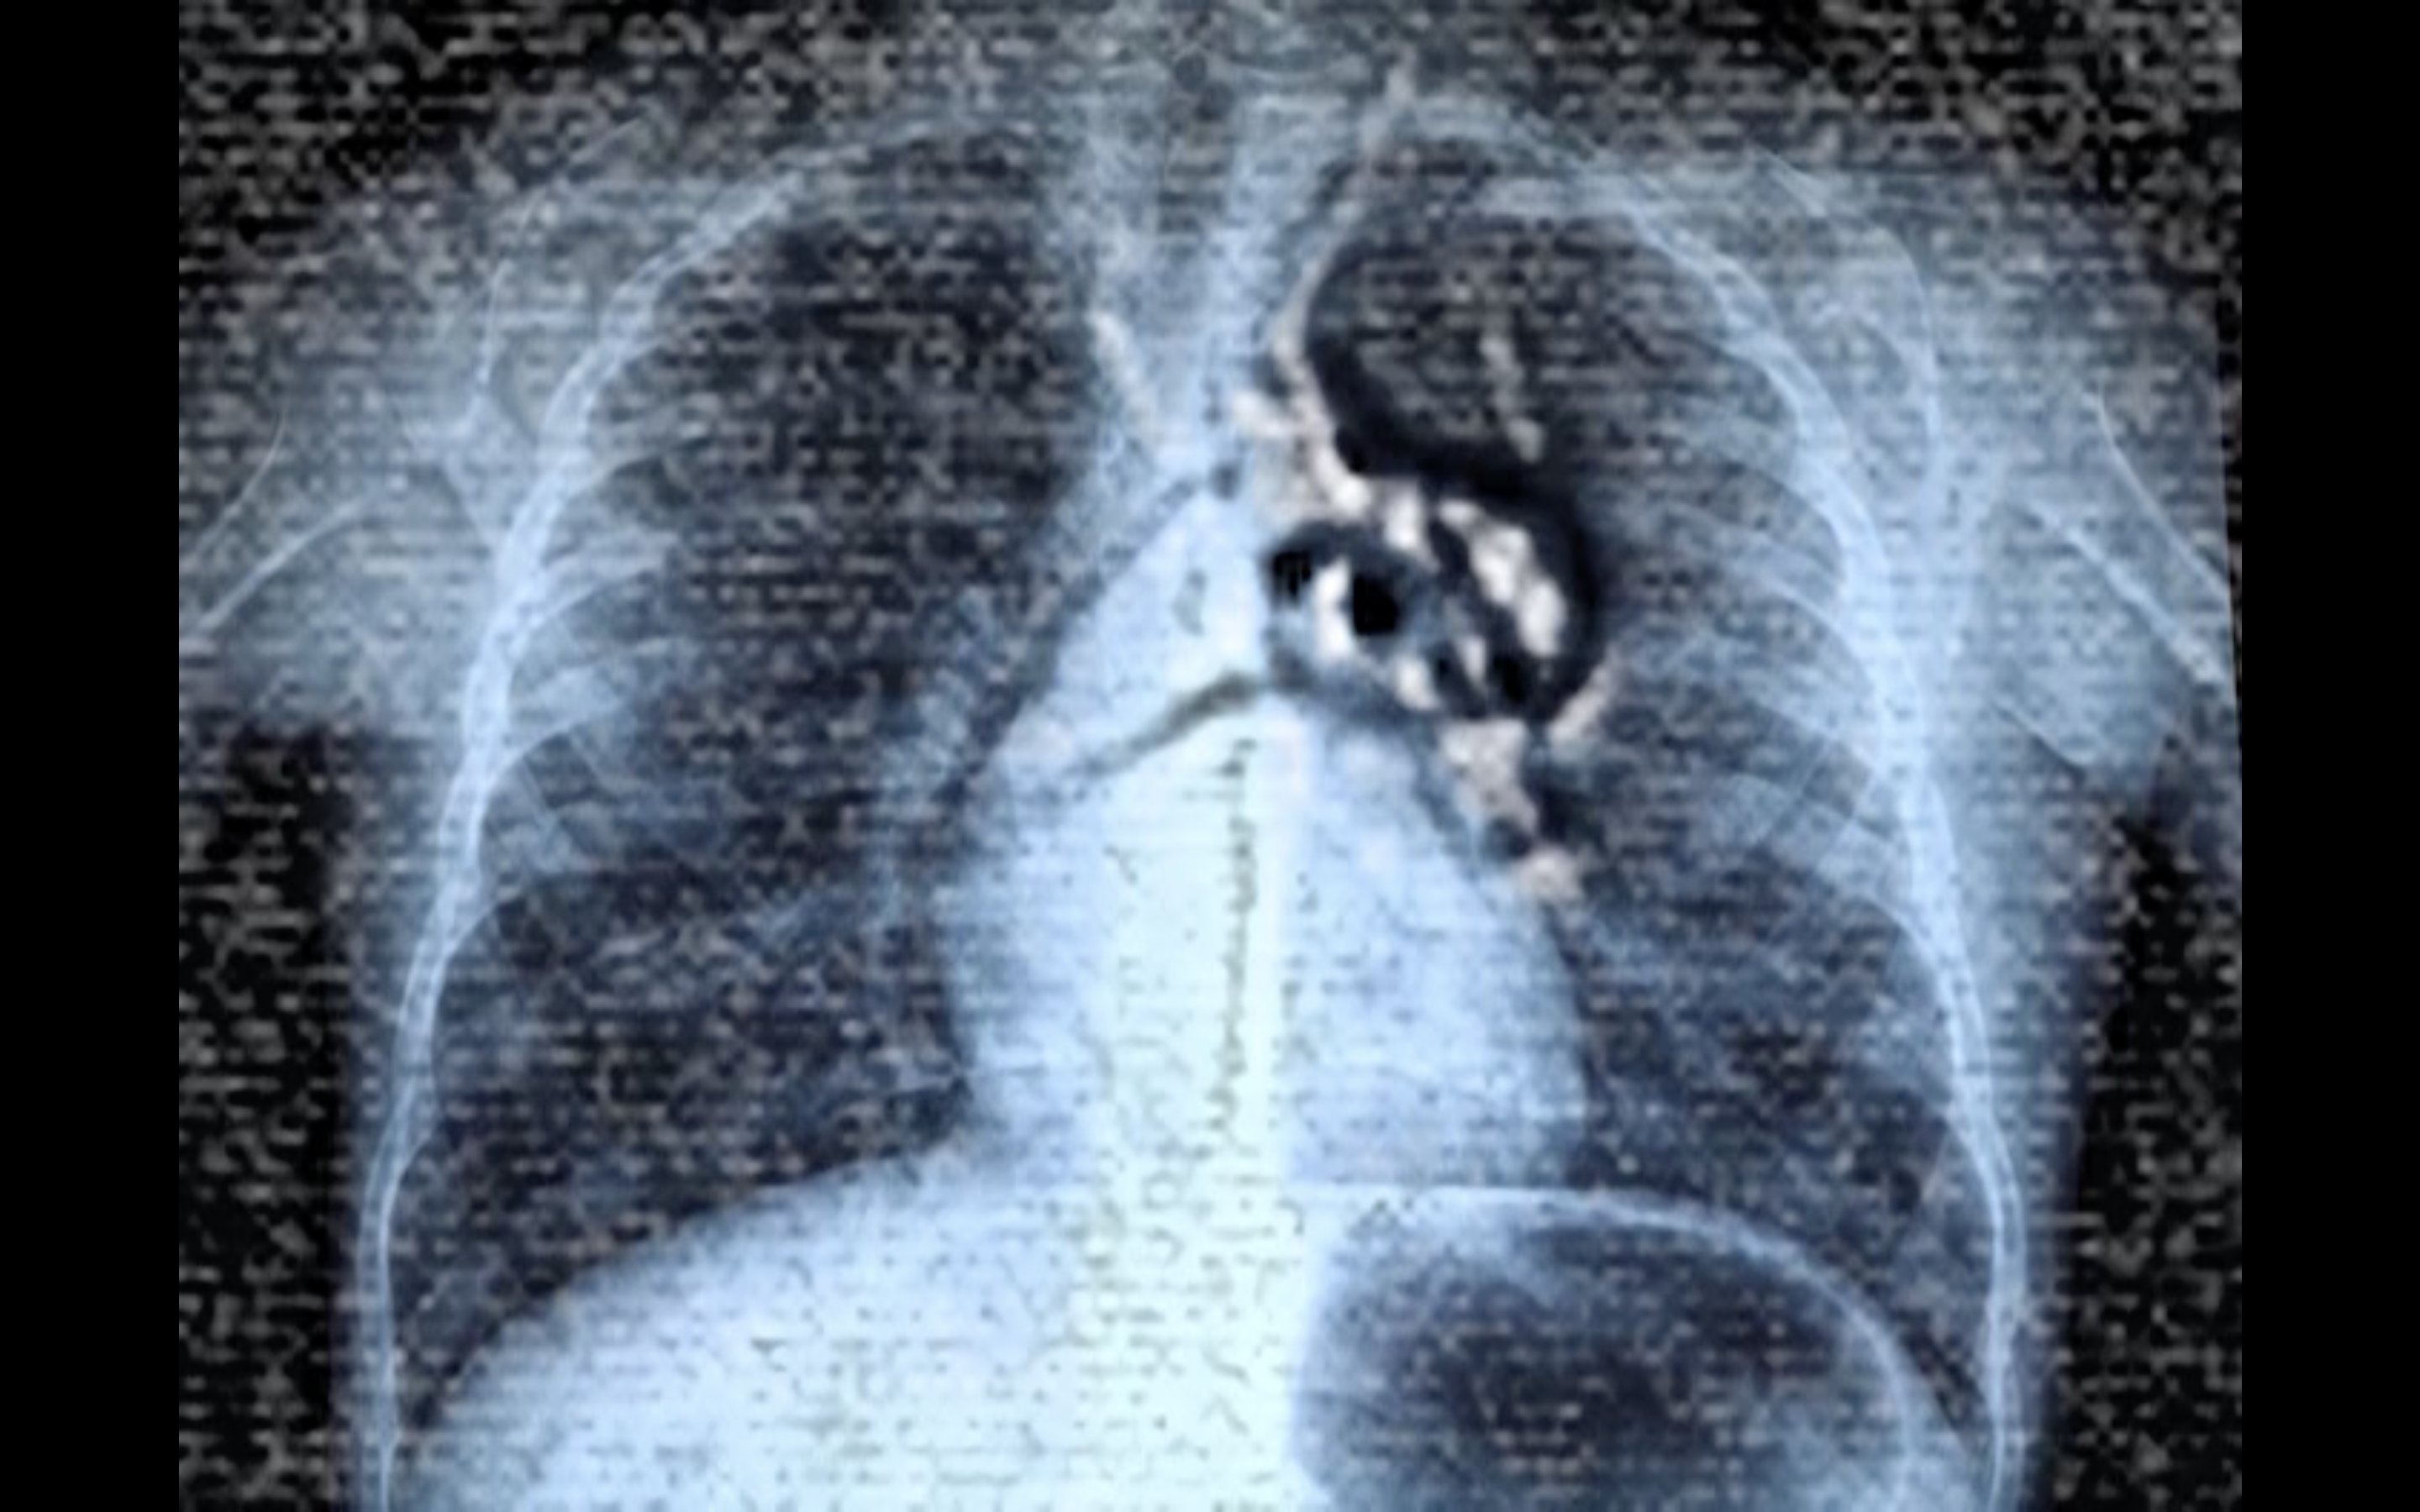

For our issue on The Edges of Conservation, you propose a film with the polysemous title X-hale: It shows an X-ray image of a body that seems to be inhabited by moving organisms, while an intermittent Indonesian voiceover is heard and fragments of a poem in several languages flicker across the screen. What do we see?

Aram Lee : The work started from an exchange I had with a Chinese Indonesian colleague and friend, Francisca Angela, also a resident at Rijksakademie. Both of us had to undergo a medical exam to diagnose tuberculosis when we arrived in the Netherlands. The exam involves medical imagery: You hold a metal plate to your chest and then hold your breath while an X-ray image is made of the lungs. In my work, I combined the medical image of my own body with the images that I had made under the microscope in collaboration with the immunologist Juan J. Garcia Vallej of the Microbes Laboratory at Amsterdam UMC: we analyzed a water droplet from the basement of the Wereldmuseum Amsterdam that had dripped through the museum’s thick foundations. The test revealed 95 living cultures within that droplet. In spite of all the museum’s efforts to seal its walls and shield their collections from the outside world, thousands of living organisms still managed to infiltrate through the walls in microscopic quantities of water. I was interested in the porosity that became apparent in this process. The museum’s goal of creating a conservation space that could effectively separate inside and outside had failed.

LA : In your film, you overlay footage of the living organisms with the X-ray images of your chest – visually, they inhabit your body, as your lungs are circumspectly examined.

AL : The filmic collage combines my personal, lived corporeal experience, which became an object of medical examination, with the microscopic images of the microbes in the water droplets at the museum. It considers the body as a geopolitical locus, as a territory under surveillance to distinguish registered, authorized, and legalized bodies from those considered a danger, or as stowaways, illegal entities, bodies crossing borders without permission.

LA : X-ray has repeatedly been used in feminist experimental filmmaking, often to refer to the vulnerability of the body, and its “over-exposure” by technology and patriarchy1. In addition to the fragility of the body as displayed in the x-ray images, in your film you bring the images of the moving microbes to your body. Thereby, you operate a shift, whereby your body and the transparent and “overexposed” medical images of your lungs scrutinized with suspicion by a public health service enacting geographical, bodily controls while attributing degrees of potential danger to them, now becomes the support that allows the microbes to move freely. As if confirming the suspicion of the public health authorities, you visually contaminate your body, inscribing living cultures within it that transgress walls without permission. When watching the film, there is an uncertainty whether these are images of disease gaining space in the human body, or whether they are beneficial parts of the body’s vital processes?

Aram Lee: X-Hale, 2024. Film Still.

Aram Lee: X-Hale. 2024. Film Still.